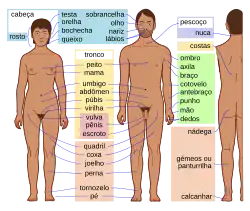

O tórax[1] é uma parte da anatomia dos mamíferos e outros animais tetrápodes localizada entre o pescoço e o abdômen.[2][3] Em insetos, crustáceos e nos extintos trilobitas, o tórax é uma das três principais divisões do corpo da criatura, cada uma das quais, por sua vez, é composta de múltiplos segmentos.

O tórax humano inclui a cavidade torácica e a parede torácica. Ele contém órgãos, incluindo o coração, os pulmões e o timo, bem como músculos e várias outras estruturas internas. Muitas doenças podem afetar o tórax, e um dos sintomas mais comuns é a dor torácica.